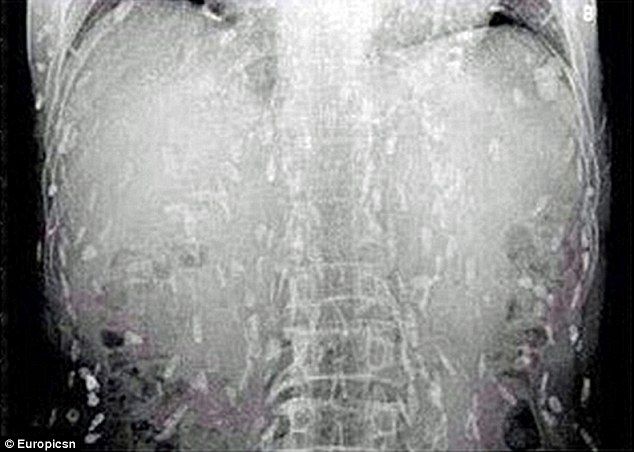

寿司好きの男性が体か痒い、胃が痛いと病院に行ったところ、全身から寄生虫が発見されるというショッキングな出来事がありました。中国のその男性は生魚のスライスを多く食べていたといいます。

感染すると数週間ほどで15mまで成長し、そして何年にもわたって生き続けます。場合によっては腸管以外の場所にも移動し、そこで卵を産み付けるのです。症状は疲労、便秘、腹部の不快感などと少なく、患者は比較的穏やかに過ごします。しかし最終的には肝臓、眼、心臓や脳などに寄生虫が移動し、その部位を食べることで生命を脅かす可能性があります。